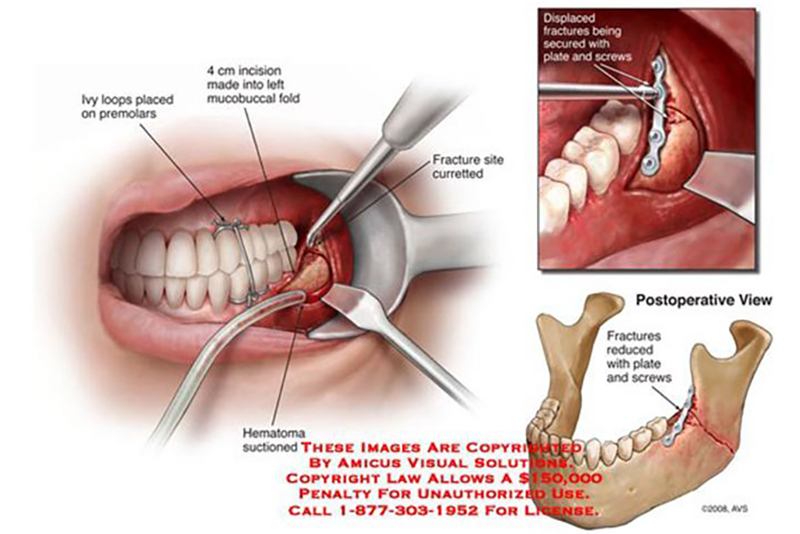

- Damaged blood vessels will result from radiation therapy for cancer treatment in 12 to 15 percent of patients. This most commonly results in osteoradionecrosis of the jaw, radiation cystitis, proctitis and damage to skin from radiation for breast cancer. Damaged blood vessels also result from crush injuries and surgical procedures.

- Promotes collagen, bone and cartilage repair and regeneration. Enhances osteogenesis by stimulating osteoclastic and osteoblastic activity which is especially important in treating osteoradionecrosis and osteomyilitis.

- Stimulates capillary angiogenesis in soft tissue and bone. This is especially important in treating diabetic wounds and radiation injury such as osteoradionecrosis, proctitis and radiation cystitis.